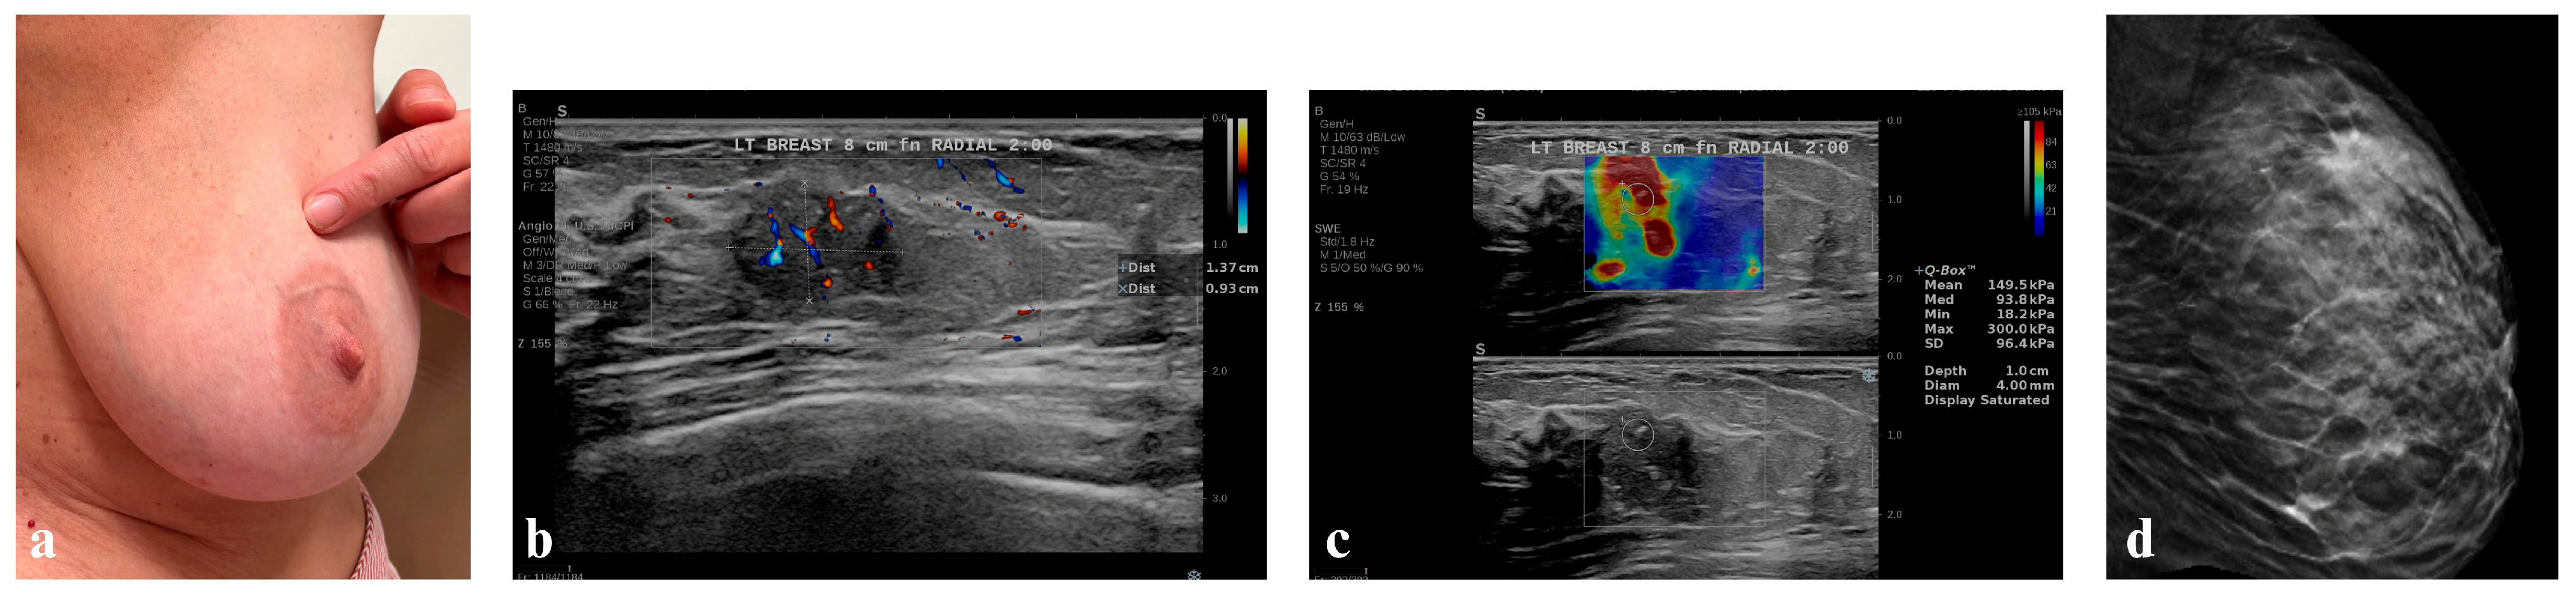

- At starting session (I session). In the initial session of the four-day workshop, all four groups (A–D) of students (Group A on day 1, Group B on day 2, etc.) were independently provided with the same clinical image of the patient with left breast abnormality that had been retrieved by the project developers (Figure 3) and assigned the task to formulate a medical diagnosis in the form of a single sentence within 5 min.

- In the third (III) session, each group of medical students (Groups A, B, C, and D) displayed a case study with clinical images of four different patients: Group A—Figure 4, Group B—Figure 5, Group C—Figure 6, Group D—Figure 7. The students were then asked to formulate an interpretation of all signs and symptoms they see.

3.5.1. Patient of Group A